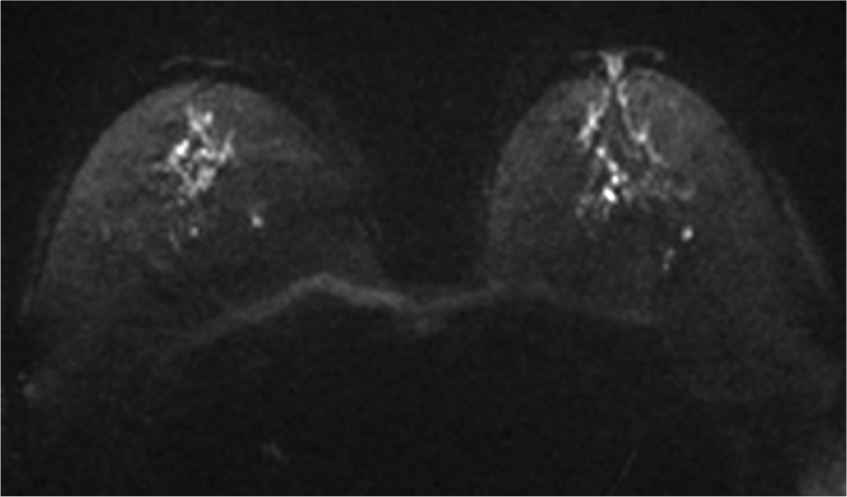

5. Ultrafast DCE

超早期相では、DCISの病変(矢印)は、超早期(8相目: 造影剤注入25.7秒後)から急速に造影され、BPEの影響を受けることなく病変を認識することができる。DCISの病変は、区域性の分布を示しているが、乳頭下には腫瘍の進展を疑うような造影域は認めない。